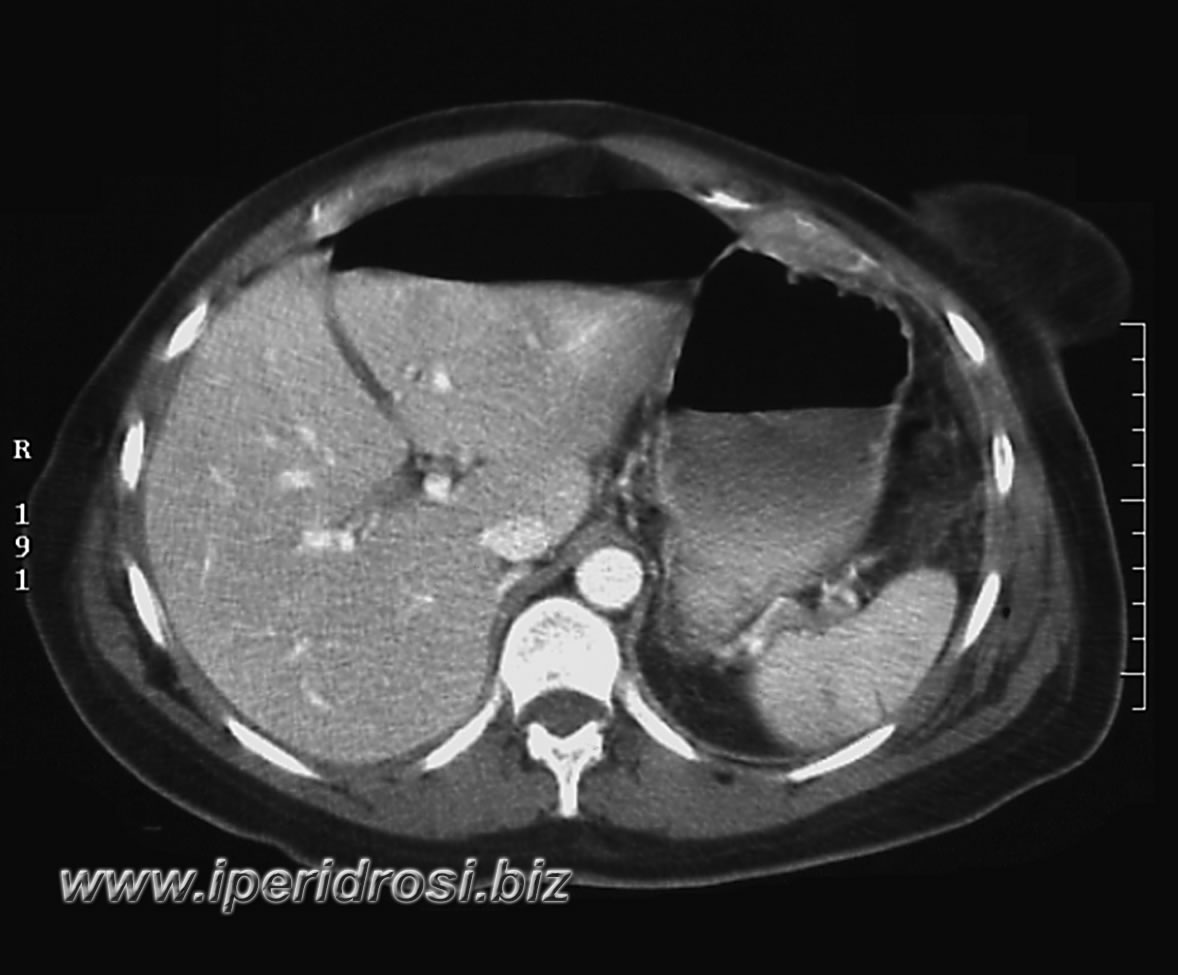

Torace: a sinistra abbondante versamento pleurico e parzialmente saccato, atelettasia parenchimale basale bilaterale più evidente a sinistra dove residua limitato parenchima ventilato.

Addome: abbondante versamento addomino-pelvico diffuso con falda aerea piuttosto abbondante all'addome superiore. Rene a ferro di cavallo con cisti parapieliche a sinistra. Distensione del colon da meteorismo ed ispessimento delle pareti intestinali con iperemia di numerose anse.